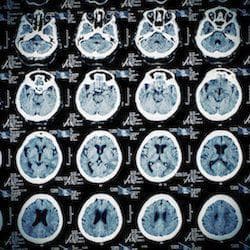

Traumatic Brain Injuries

Traumatic brain injuries are caused by a blunt force strike to the head, or by the penetration of a foreign object into the skull. The CDC notes that not all blunt force trauma to the head results in a traumatic brain injury, though traumatic brain injuries can range from mild to severe. Temporary amnesia, for example, is a mild traumatic brain injury, while extended loss of consciousness, brain function, or long-term memory loss are examples of severe traumatic brain injury.